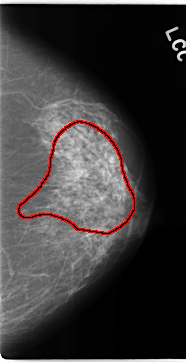

C_0133_1.LEFT_MLO

C_0133_1.LEFT_CC

FILE: C_0133_1.LEFT_CC.OVERLAY

TOTAL_ABNORMALITIES 1

ABNORMALITY 1

LESION_TYPE CALCIFICATION TYPE AMORPHOUS DISTRIBUTION REGIONAL

ASSESSMENT 4

SUBTLETY 3

PATHOLOGY MALIGNANT

TOTAL_OUTLINES 1

BOUNDARY